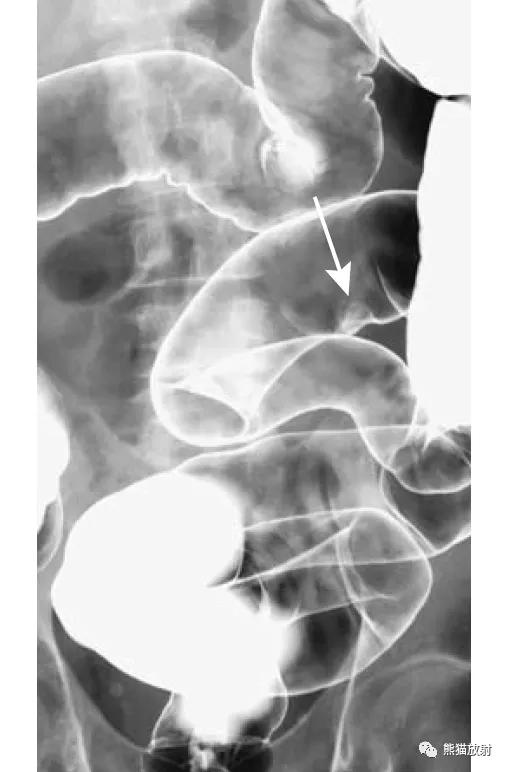

结-结肠肠套叠,由盲肠癌所致。钡灌肠显示横结肠中的肠套叠(箭头),在进一步的压力下,肠套叠移位至升结肠。

回-结肠套叠。CT定位像示7岁患儿的肠套叠(箭头)。Burkitt淋巴瘤所致。右图:10个月大的婴儿,疼痛和右上腹肿块。X线平片示横结肠(箭头)区域有软组织肿块。钡灌肠证实为肠套叠。